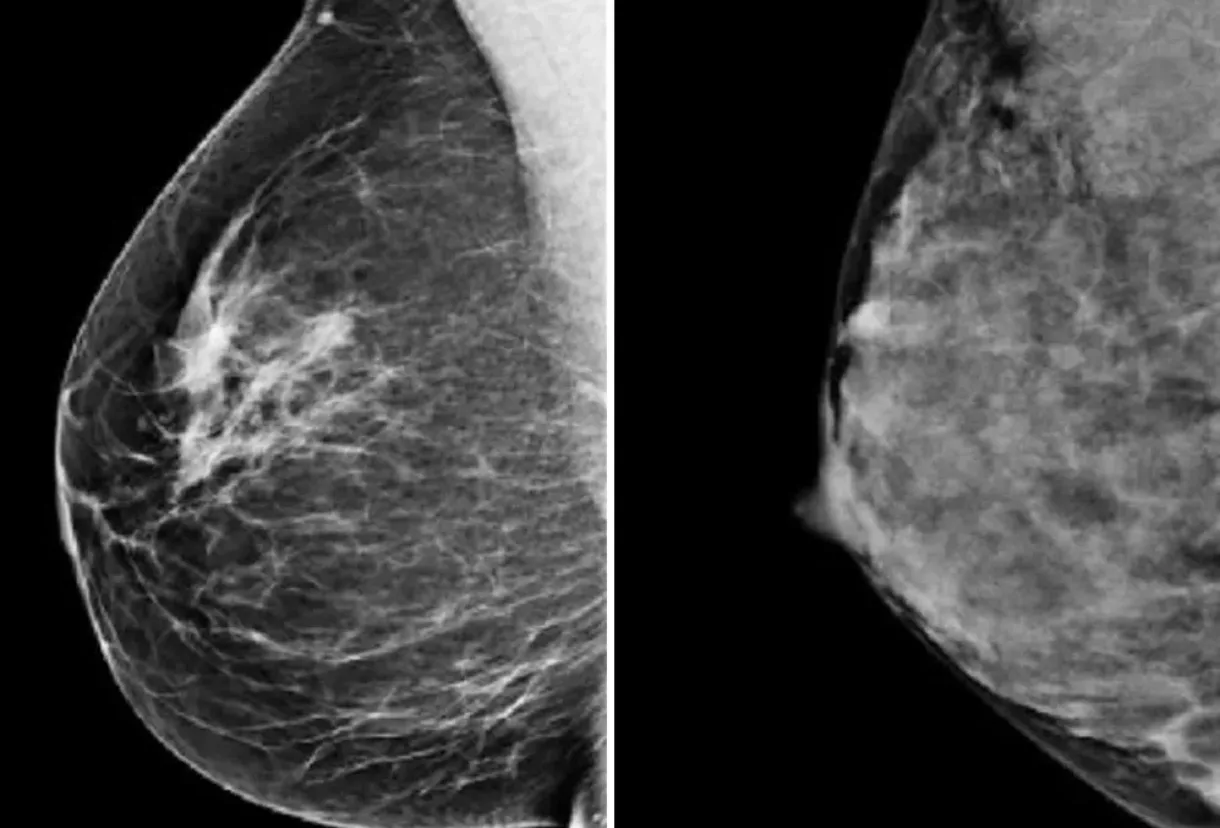

Enhanced breast cancer screening could help more women with dense breasts - Canc